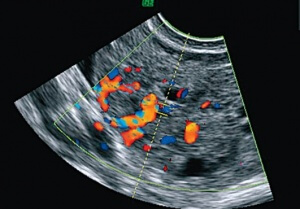

Если при проведении ультразвукового исследования на экране можно увидеть, как выглядит и функционирует тот или иной обследуемый орган, то цветовое допплеровское картирование позволяет видеть в режиме реального времени все движущиеся жидкости в этом органе и вокруг него. То есть можно не просто увидеть, в каком состоянии находятся сосуды органа, но и отследить движение жидкости.

Мало того, цветовое картирование позволяет обозначить потоки крови с разной скоростью движения различными цветами, то есть создает цветовую картину сосудистой системы органа. Можно в подробностях увидеть структуру и работу каждого отдельного сосуда, выявить патологии самих сосудов, а также обнаружить опухоли — в них отсутствует обычная система кровоснабжения.

Она особенно необходима в том случае, если предполагаемая патология имеет прямую или косвенную связь с работой или состоянием сосудов. Если при ультразвуковом исследовании на экране монитора появляется только черно-белое изображение, то цветовое картирование показывает цветные элементы в области исследования. Нужно понимать, что красный и синий цвет означает не вены и артерии, а демонстрирует направление движения крови — от датчика или к нему. Опытный специалист в этой области отлично знает все тонкости такого способа диагностирования, а специальные таблицы на экране прибора помогают в проведении точной оценки проблем.